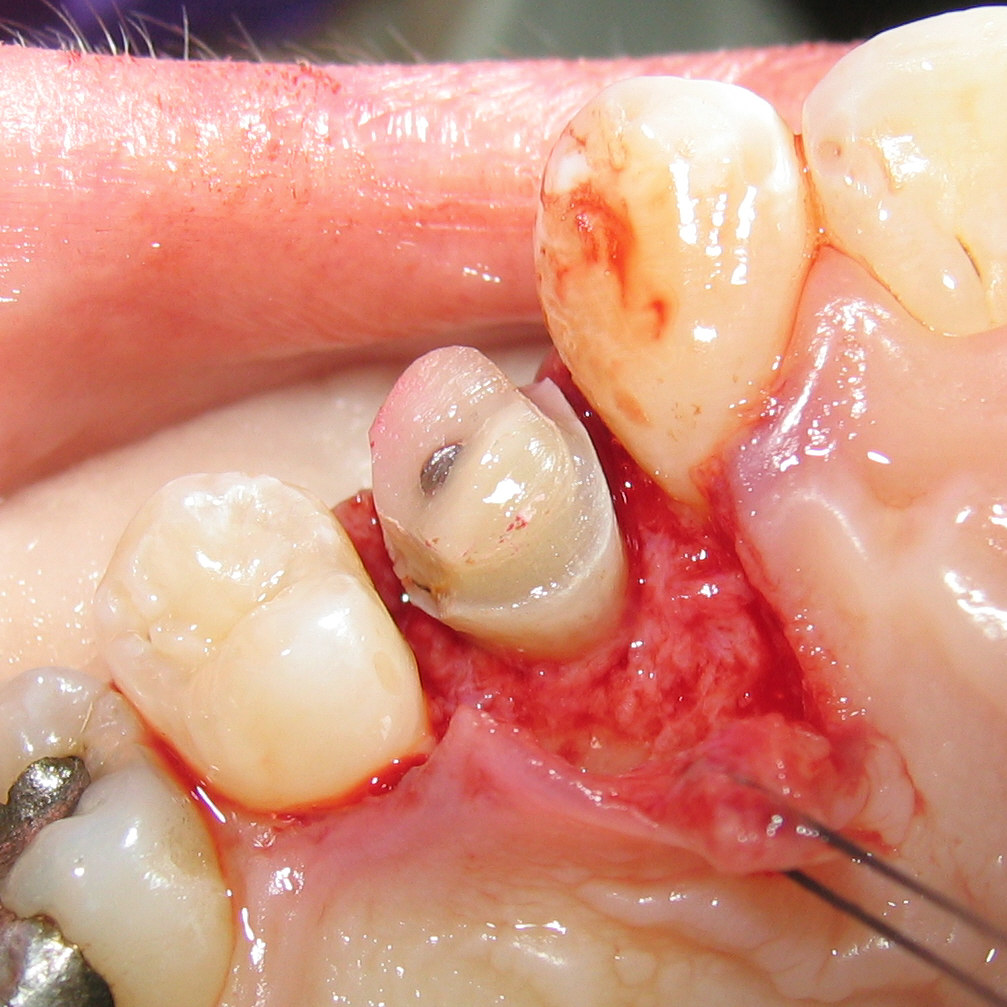

Crown lengthening is performed under local anesthetic to numb the area. The time that it takes for this procedure depends on the number of teeth that need to be treated. Any dental crowns that were present prior to the procedure, have to be removed and placed back afterwards. Your Elgin dentist makes series of small incisions around the soft issue so they can separate the gums from the teeth. This will give the access to the roots and underlying bone.

Sometimes, removal of small amount of tissue can provide enough exposure to place the crown. In some other cases, smal amount of bone needs to be removed around the tooth which is done by special dental instruments (hand and rotary instruments).